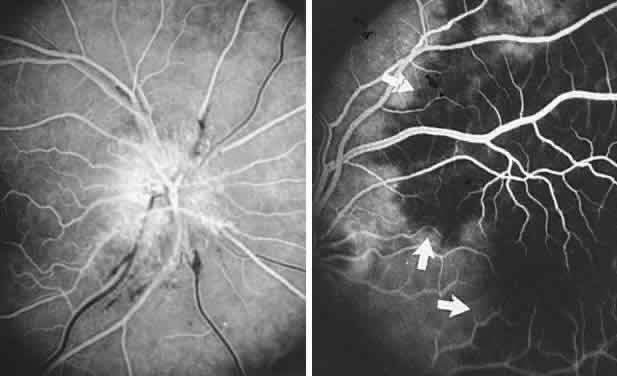

The retinal variety may be admixed in a person who suffers the more conventional attacks of migraine. It is presumed that vasospasm in the retinal circulation determines transient hypoxia, perhaps somewhat similar to the visual cortical event. On rare occasions, the fundus has been examined during typical retinal migraine episodes, and arterial constriction has been described. Wolter and Burchfield106 photographically documented such an episode and demonstrated mild “retinal edema”; vessel narrowing is also evident (Fig. 8). Fortunately, permanent complications of retinal migraine are rare. These may take the form of central retinal artery occlusion or ischemic papillopathy (see Volume 2, Chapter 16); nerve fiber bundle visual field defects may be demonstrated (Fig. 9).

Fig. 8. Retinal migraine. A. During amaurotic episode. Note the dusky appearance of the fundus, increased retinal sheen (possibly edema), and dark narrowed veins (arrows). The disc is also hyperemic. B. Fundus after episode. Compare paired arrows. (Courtesy of Dr. J. Reimer Wolter)